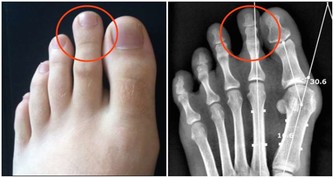

腎虛的症狀:腎陽虛的症狀為腰酸、四肢發冷、畏寒,甚至還有水腫,為“寒”的症狀,性功能不好也會導致腎陽虛;

腎陰虛的症狀為“熱”,主要有腰酸、燥熱、盜汗、虛汗、頭暈、耳鳴等。現代科學證明,當人發生腎虛時,無論腎陰虛還是腎陽虛,都會導致人的免疫能力的降低,有更多的證據表明,腎虛發生時,腎臟的免疫能力降低,而腎臟的微循環系統亦會發生阻塞,腎絡呈現不通。所以對於腎虛的治療應防治結合。